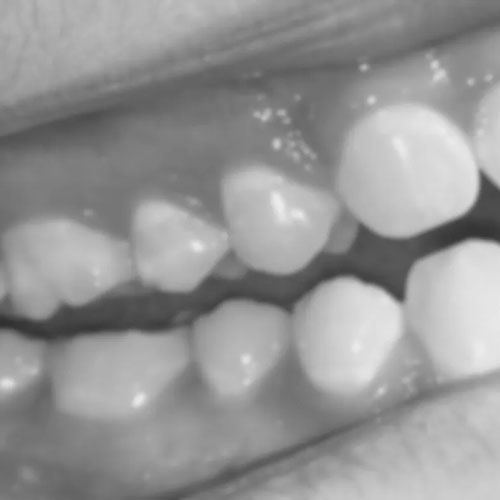

In a healthy mouth, pressure during biting and chewing is distributed evenly among all teeth. However, ankylosed teeth disrupt this balance. Because they’re anchored firmly to the jaw bone, ankylosed teeth bear less of the load, shifting more pressure onto adjacent teeth. Over time, this uneven distribution of force can cause accelerated wear, cracks, and other types of damage to neighboring teeth.

The additional pressure placed on adjacent teeth can result in noticeable wear over time. This wear often manifests as flattened or chipped edges and can make teeth more susceptible to decay. Furthermore, the uneven force may exacerbate issues like temperature sensitivity and can increase the risk of fractures. In extreme cases, the compromised teeth may even require extraction.